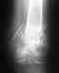

Осколки 5 плюсневой кости собрали на пластину с помощью винтов. Подходят к концу отмеренные 8 недель. И теперь меня волнует, что делать после снятия лангеты? Как начать ходить? Можно ли специально тренировать ходьбу, чтобы процесс шел быстрее? Я слышала про то, что нужно носить специальные стельки. Как долго? Но не в этом главная проблема. А в том, что я занимаюсь танцами (хип-хоп, хаус, рагга, беллиданс) и йогой. Как любитель, в фитнес-клубе. Но все же это серьезно, как и нагрузки, которые бывают во время тренировок. Как скоро можно вернуться к танцам? Как долго можно заниматься? Когда можно начать прыгать, бегать? Хотя бы, что называется, в полноги? Может быть, движение наоборот поможет выздоровлению? Я прочитала, что знаменитые футболисты, получавшие подобную травму, возвращались в строй по-разному. Одни - спустя 2 месяца, другие пропускали половину сезона. И еще: справедлив ли для травматологии закон войны - бомба в одну воронку не падает? Словом, можно ли сломать кость в том же самом месте, если перегнуть палку?